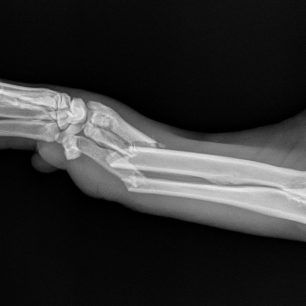

Η κα Μακρή δημοσίευσε σήμερα στο facebook την γνωμάτευση του κτηνιάτρου σχετικά με την εξέλιξη της υγείας του ζώου. Σε αυτή αναφέρεται ότι: «Ο σκύλος έφερε συντριπτικά ενδοαρθρικά κατάγματα με μετατόπιση στο κάτω τρίτο του αριστερού αντιβραχίου και στο κάτω τρίτο του αριστερού μηριαίου. Ολοκληρώθηκε με επιτυχία η πρώτη χειρουργική επέμβαση που αφορούσε την ανάταξη και οστεοσύνθεση του αριστερού αντιβραχίου. Λόγω της σοβαρότητας του κατάγματος η διάρκεια της χειρουργικής επέμβασης ήταν 4 ώρες και 25 λεπτά και ο σκύλος ανένηψε φυσιολογικά».